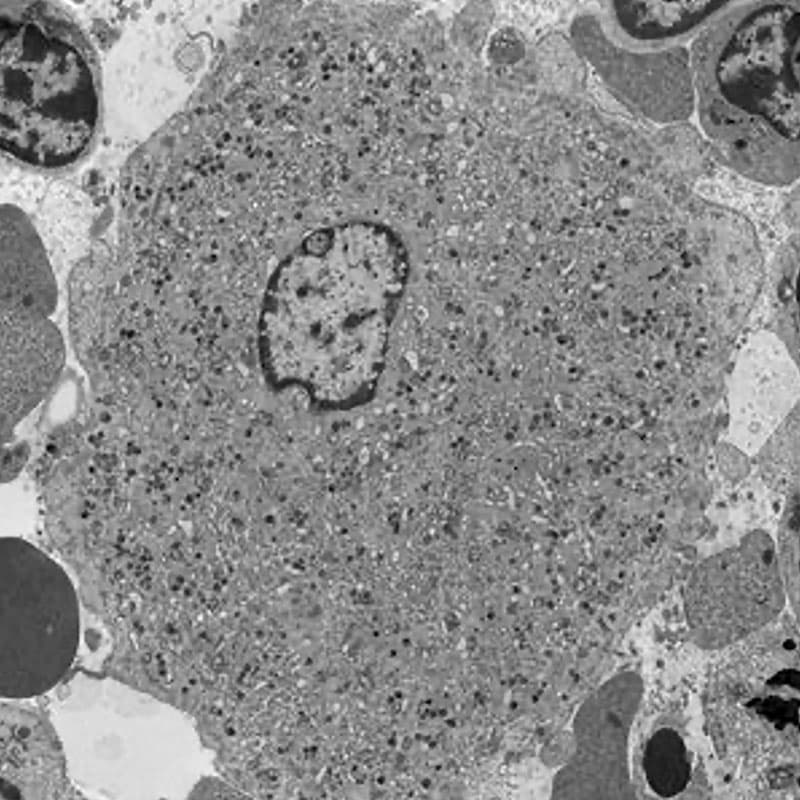

Transmission electron microscopy of a mouse bone marrow megakaryocyte.

Fig.1. Transmission electron microscopy of a mouse bone marrow megakaryocyte.

Blood platelets are produced in the bone marrow by megakaryocytes in unique processes that require polyploidisation and extensive membrane rearrangements. These include the formation of the demarcation membrane system, the surface-connected membrane reservoir for future platelets. As megakaryocytes mature, the demarcation membrane system initiates as a single plasma membrane invagination that extends between the lobes of the polyploid nucleus and further expands into its mature form by addition of intracellular membrane materials that are biosynthesized in the endoplasmic reticulum or transported from the Golgi apparatus. The precise molecular mechanisms responsible for these unique membrane rearrangements remain poorly understood. Our current research is focused on the role of receptor-mediated endocytosis in platelet production and function, focusing on the F-BAR protein PACSIN2 and the large GTPase dynamin 2.